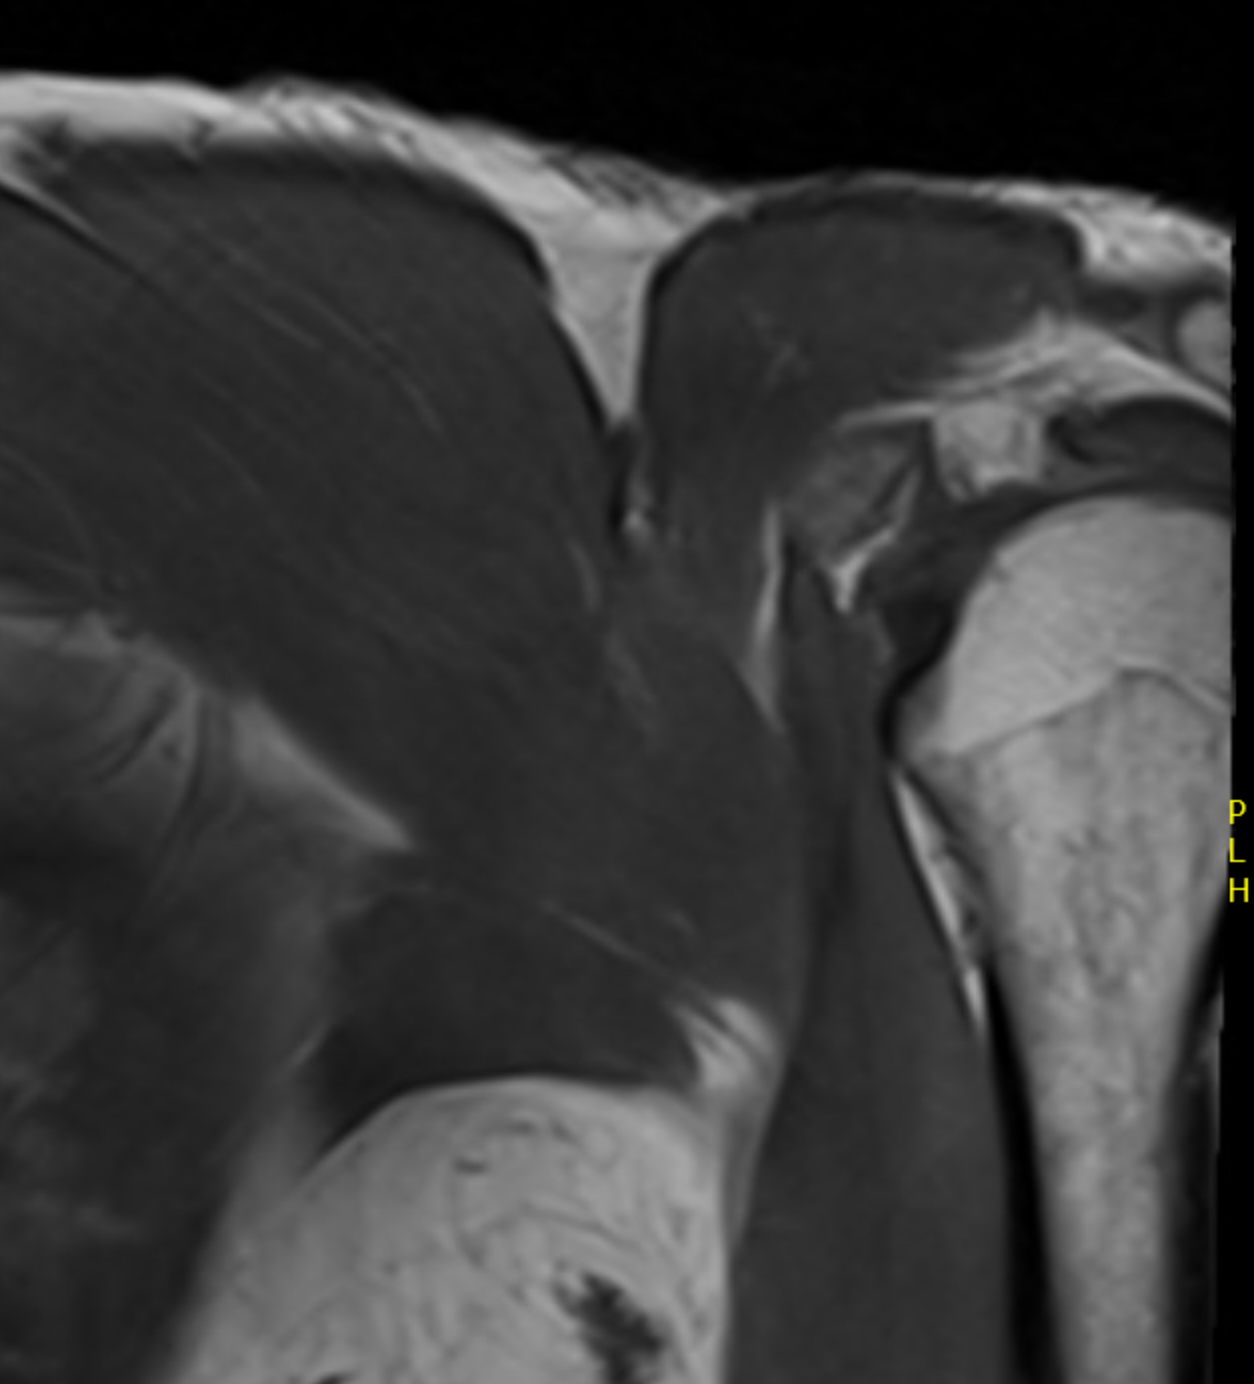

pecpecpec

Coronal T2 Right shoulder demonstrating tendon avulsion of both sternal and clavicular heads

pec tearPec tear

Axial T2 Right shoulder demonstrating tendon avulsion of both sternal and clavicular heads